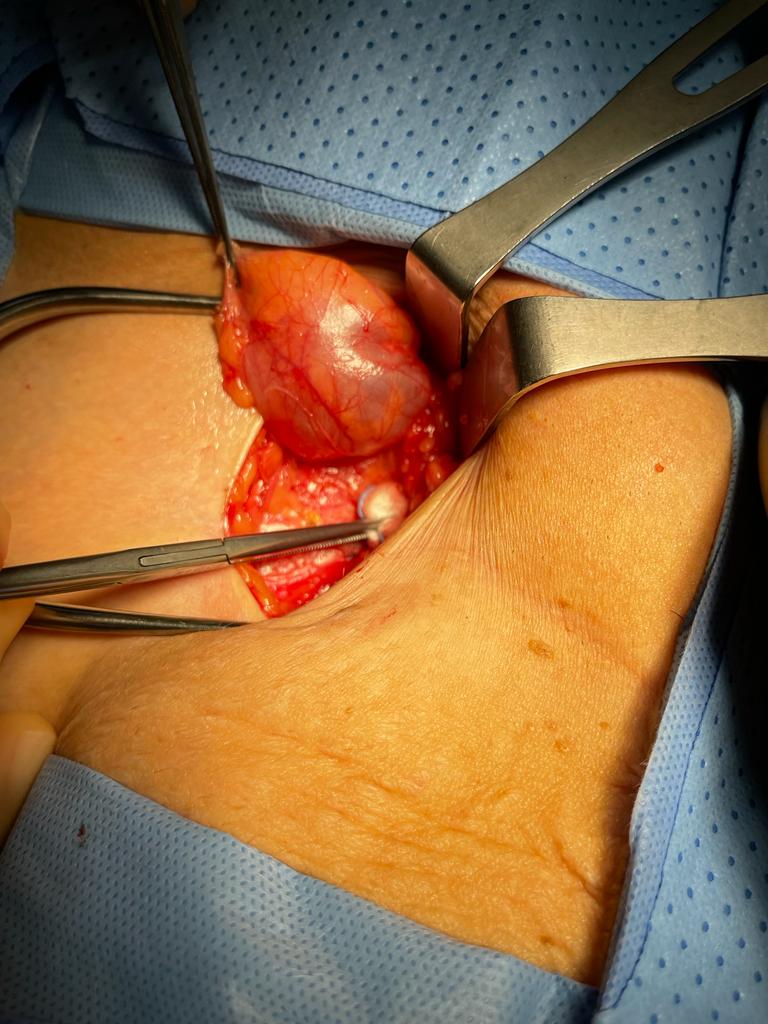

Surgical treatment for a cyst in the Canal of Nuck consists of two components: the excision of the cystic structure and the simultaneous closure of the inguinal defect, which can be done with or without mesh. The cyst can be removed surgically, and the prosessus vaginalis can be closed, which may make it feasible to reduce the frequency with which the condition returns. The choice of the most effective surgical procedure is based on various factors, including the seriousness of the underlying disorder, the presence of an inguinal hernia, the accuracy of the preoperative diagnosis, and a few other considerations [1].

Depending on the circumstances, if an inguinal hernia is discovered simultaneously, a hernia repair may be performed concurrently, with or without mesh insertion. When the mass extends to the labia majora, an extra vulva repair could be recommended as a treatment option. An intraoperative photograph of a hydrocele of the canal of Nuck is shown in Figure 3.